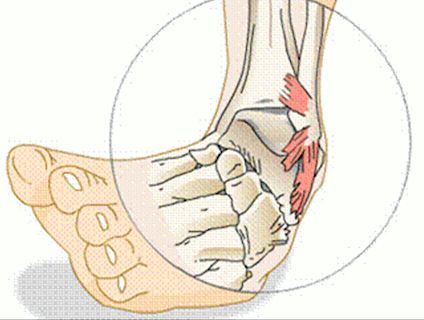

- подтаранний вивих стопи виникає як наслідок різко підвернути стопи. Травму нерідко супроводжують розриви зв'язок і супутні переломи.

вивих щиколотки

Вивих стопи в гомілковостопному суглобі - одна з найважчих травм, сполучена з розривом зв'язок, переломом щиколотки і внутрішньосуглобових переломами. Складний вивих вимагає ретельної діагностики та максимально точного відновлення уламків кісткової і суглобової тканин.